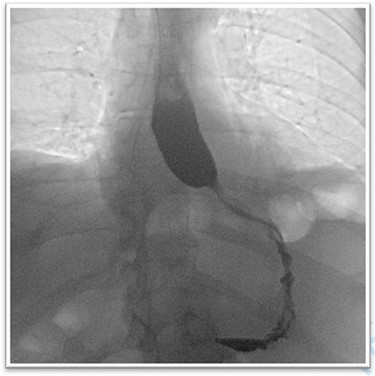

We restricted the intervention to an anatomical repair of the hiatal region. Fundoplication was not indicated because preoperative examination revealed no symptoms of reflux disease. The first three postoperative days were uneventful, and the patient responded well to puréed food. After receiving solid food on postoperative day four, the patient was regurgitating multiple times per day and complaining of globus sensation. A contrast-enhanced oesophagogram showed near-complete stenosis of the esophagogastric junction (Fig. 4). Gastroscopy was crucial to avoid an unnecessary surgical exploration as it showed the stenosis was not of mechanical origins such as a too tight hiatoplasty or fundoplication but was caused by a food bolus hindering optimal passage. The bolus was removed during gastroscopy and globus sensation disappeared thereafter. The remaining postoperative period was uneventful, with normal diet and no feelings of retrosternal pressure at hospital discharge.

The barium oesophagogram showing a near to total stenosis caused by alimentary bolus.